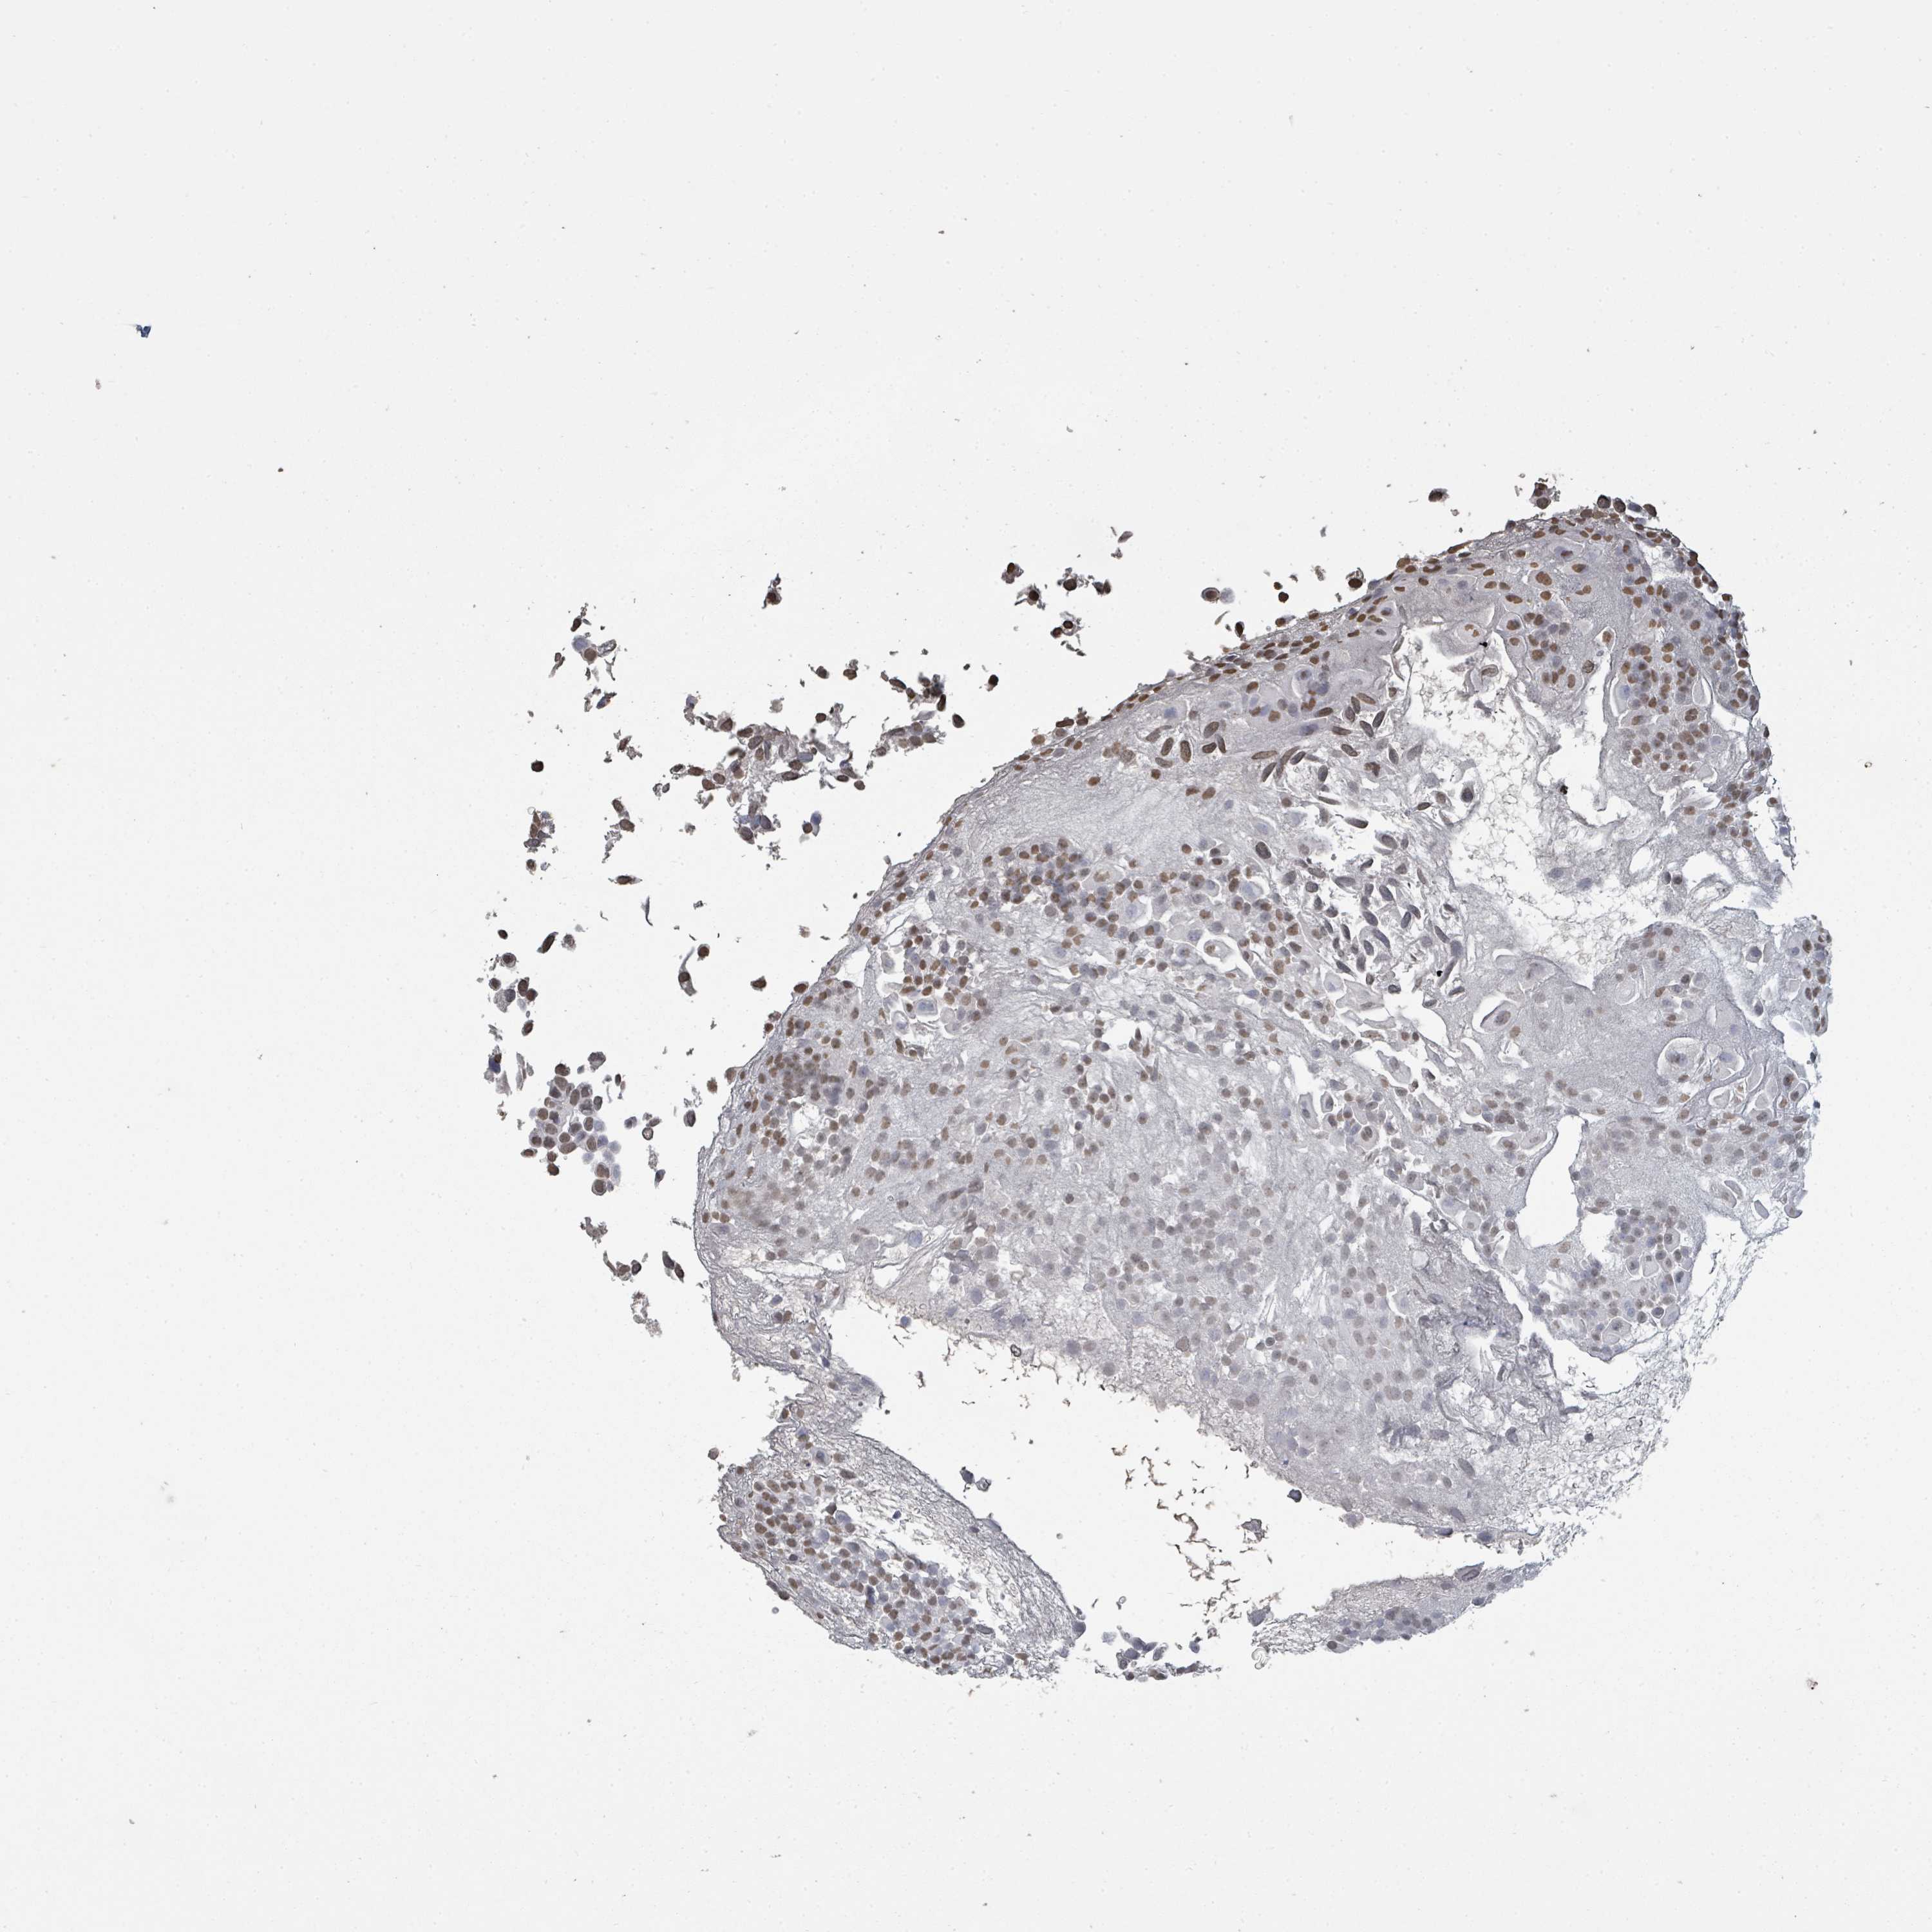

UROTHELIAL CANCER - Protein expressioni

A mouse-over function shows sample information and annotation data. Click on an image to view it in a full screen mode. Samples can be filtered based on level of antibody staining by selecting one or several of the following categories: high, medium, low and not detected. The assay and annotation is described here.

Antibody stainingi

Antibody staining in the annotated cell types in the current human tissue is reported as not detected, low, medium, or high, based on conventional immunohistochemistry profiling in selected tissues. This score is based on the combination of the staining intensity and fraction of stained cells.

Each image is clickable and will lead to virtual microscopy that enables deeper exploration of all samples and also displays staining intensity scores, fraction scores and subcellular localization as well as patient and tissue information for each sample.

Antibody HPA046775

Antibody HPA050633

Staining

High

Medium

Low

Not detected

Intensity

Strong

Moderate

Weak

Negative

Quantity

>75%

75%-25%

<25%

None

Location

Nuclear

Cytoplasmic/membranous

Cytoplasmic/membranous,nuclear

Urothelial carcinoma, High grade